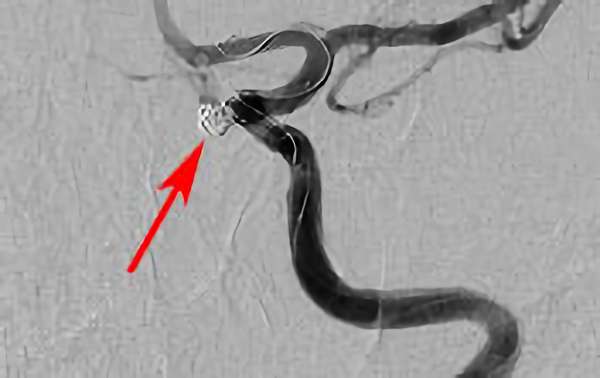

No.1631 手術中